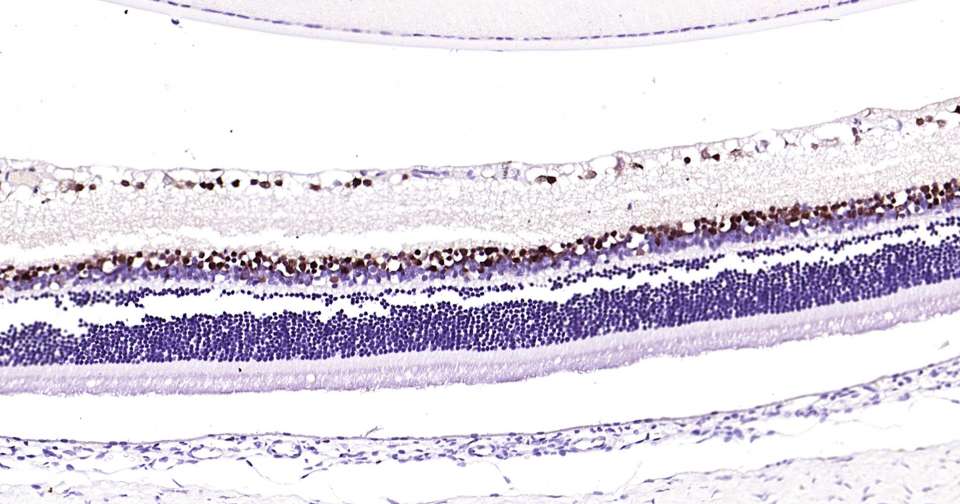

Immunohistochemical analysis of paraffin embedded rat eye tissue slide using IHC0367R (Rat PAX6 Kit).